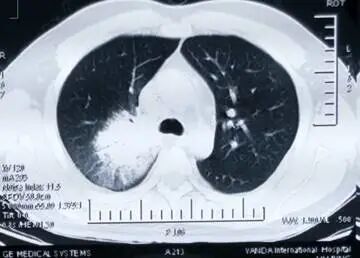

胸部CT(2017-11-8)

肺内结节得到好转吸收。经治疗后患者眼部症状逐渐减轻,眼部外形恢复正常,但遗留失明。